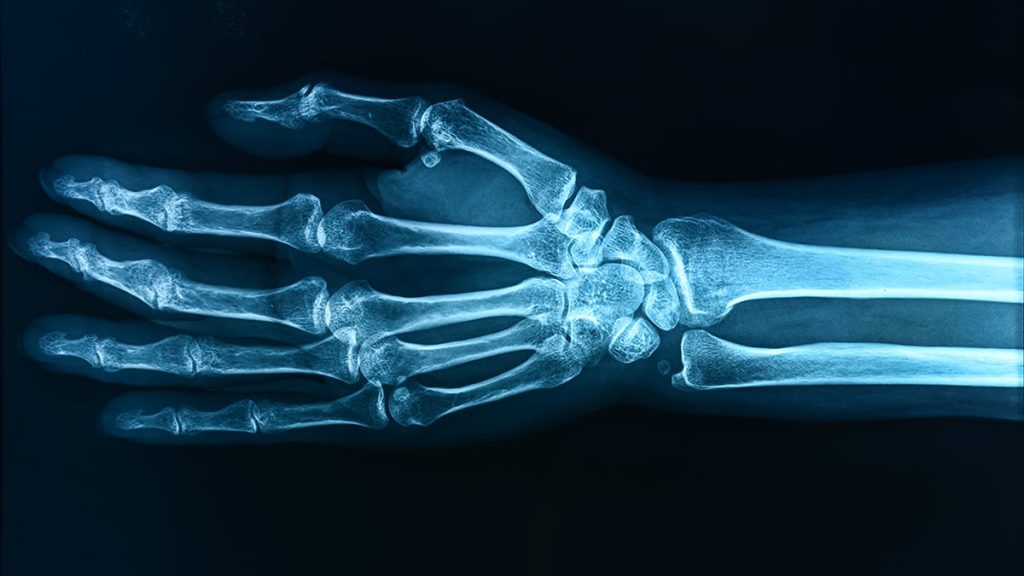

The researchers cross-referenced these levels at certain ages with measurements of bone density across different parts of the children’s skeletons.

The data showed an association between PFOA and lower forearm bone density at age 12. For the other substances scanned, associations with bone density varied with exposure time, suggesting that age is an important factor in how harmful PFAS might be.

The difference between the highest levels of PFAS and the lowest levels could work out to a roughly 30 percent higher chance of bone fracture, the researchers estimate – though it is only an estimation.

As previous studies on this issue have highlighted, lower bone mass at a young age is linked to a greater risk of bone fractures and conditions such as osteoporosis as people grow into adulthood.